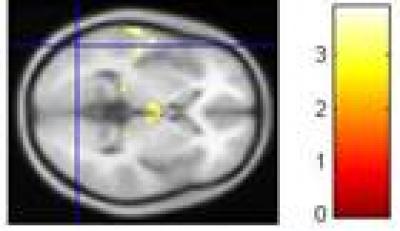

A recent study published in the Neural Regeneration Research (Vol. 8, No. 18, 2013) combined cognition tasks and functional MRI, and designed multiple repeated event-related tasks; additionally, using the International Affective Picture System-based event-related tasks, this study investigated brain functional characteristics of major depressive disorder patients exhibiting, negative bias brain imaging changes and cognitive dysfunction, as well as their relationship based on biased quantitative data. Results show that (1) the number of error responses was calculated to identify bias of emotion recognition between patients with major depressive disorder and normal controls, suggesting that the depressed patients exhibited negative bias towards emotion task stimuli based on quantitative data; (2) the activation of the occipital lobe was attenuated in depressed patients when doing emotion tasks; (3) Deficits in the occipital lobes may be an initiating factor for depression onset, which results in attention deficit disorder and cognitive dysfunction.

Article: " Abnormal activation of the occipital lobes during emotion picture processing in major depressive disorder patients," by Jianying Li1, Cheng Xu2, Xiaohua Cao1, Qiang Gao2, Yan Wang1, Yanfang Wang1, Juyi Peng1, Kerang Zhang1 (1 Department of Mental Health, First Hospital of Shanxi Medical University, Taiyuan 030001, Shanxi Province, China; 2 MRI Room, Shanxi Provincial People's Hospital, Taiyuan 030012, Shanxi Province, China)